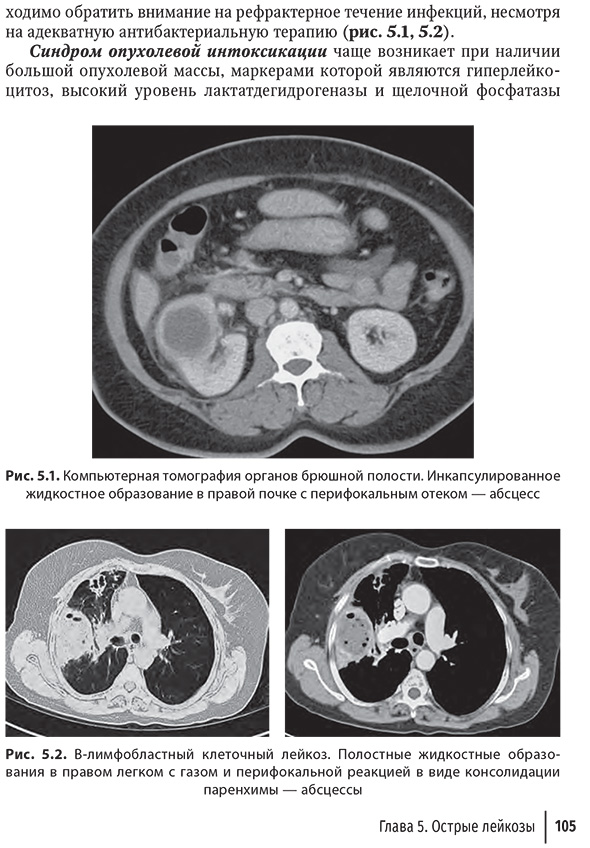

Глава 5. Острые лейкозы

и лечении острых лейкозов